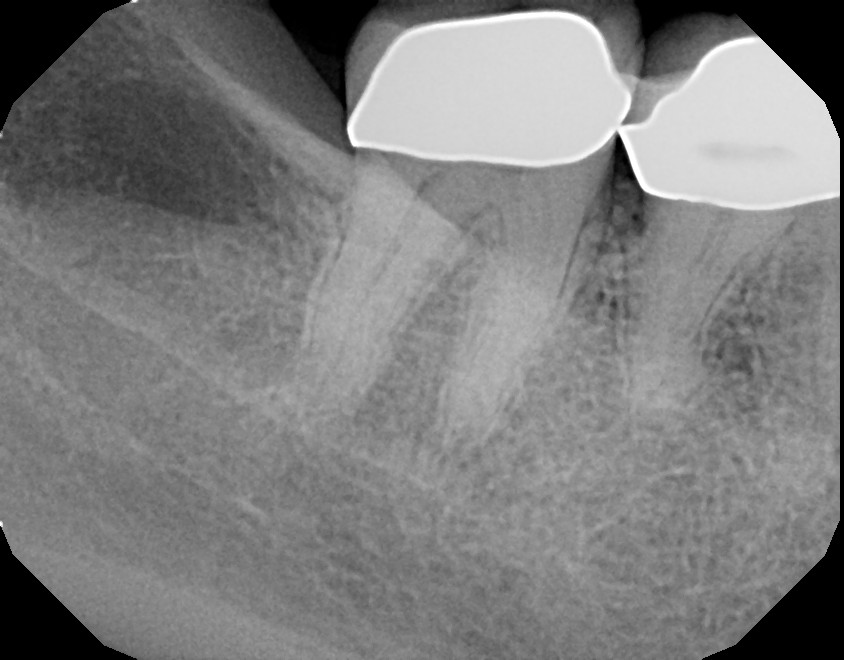

Below are pictures of a recent case of mine. This 10+ year old crown that developed decay (cavity) around the margin where tooth meets crown. Always pay attention to sensitivity around fillings and crowns and advise your dentist when symptoms develop, so you can stay away from roots canals. In this particular case, root canal was required because the decay reached too close to the nerve.